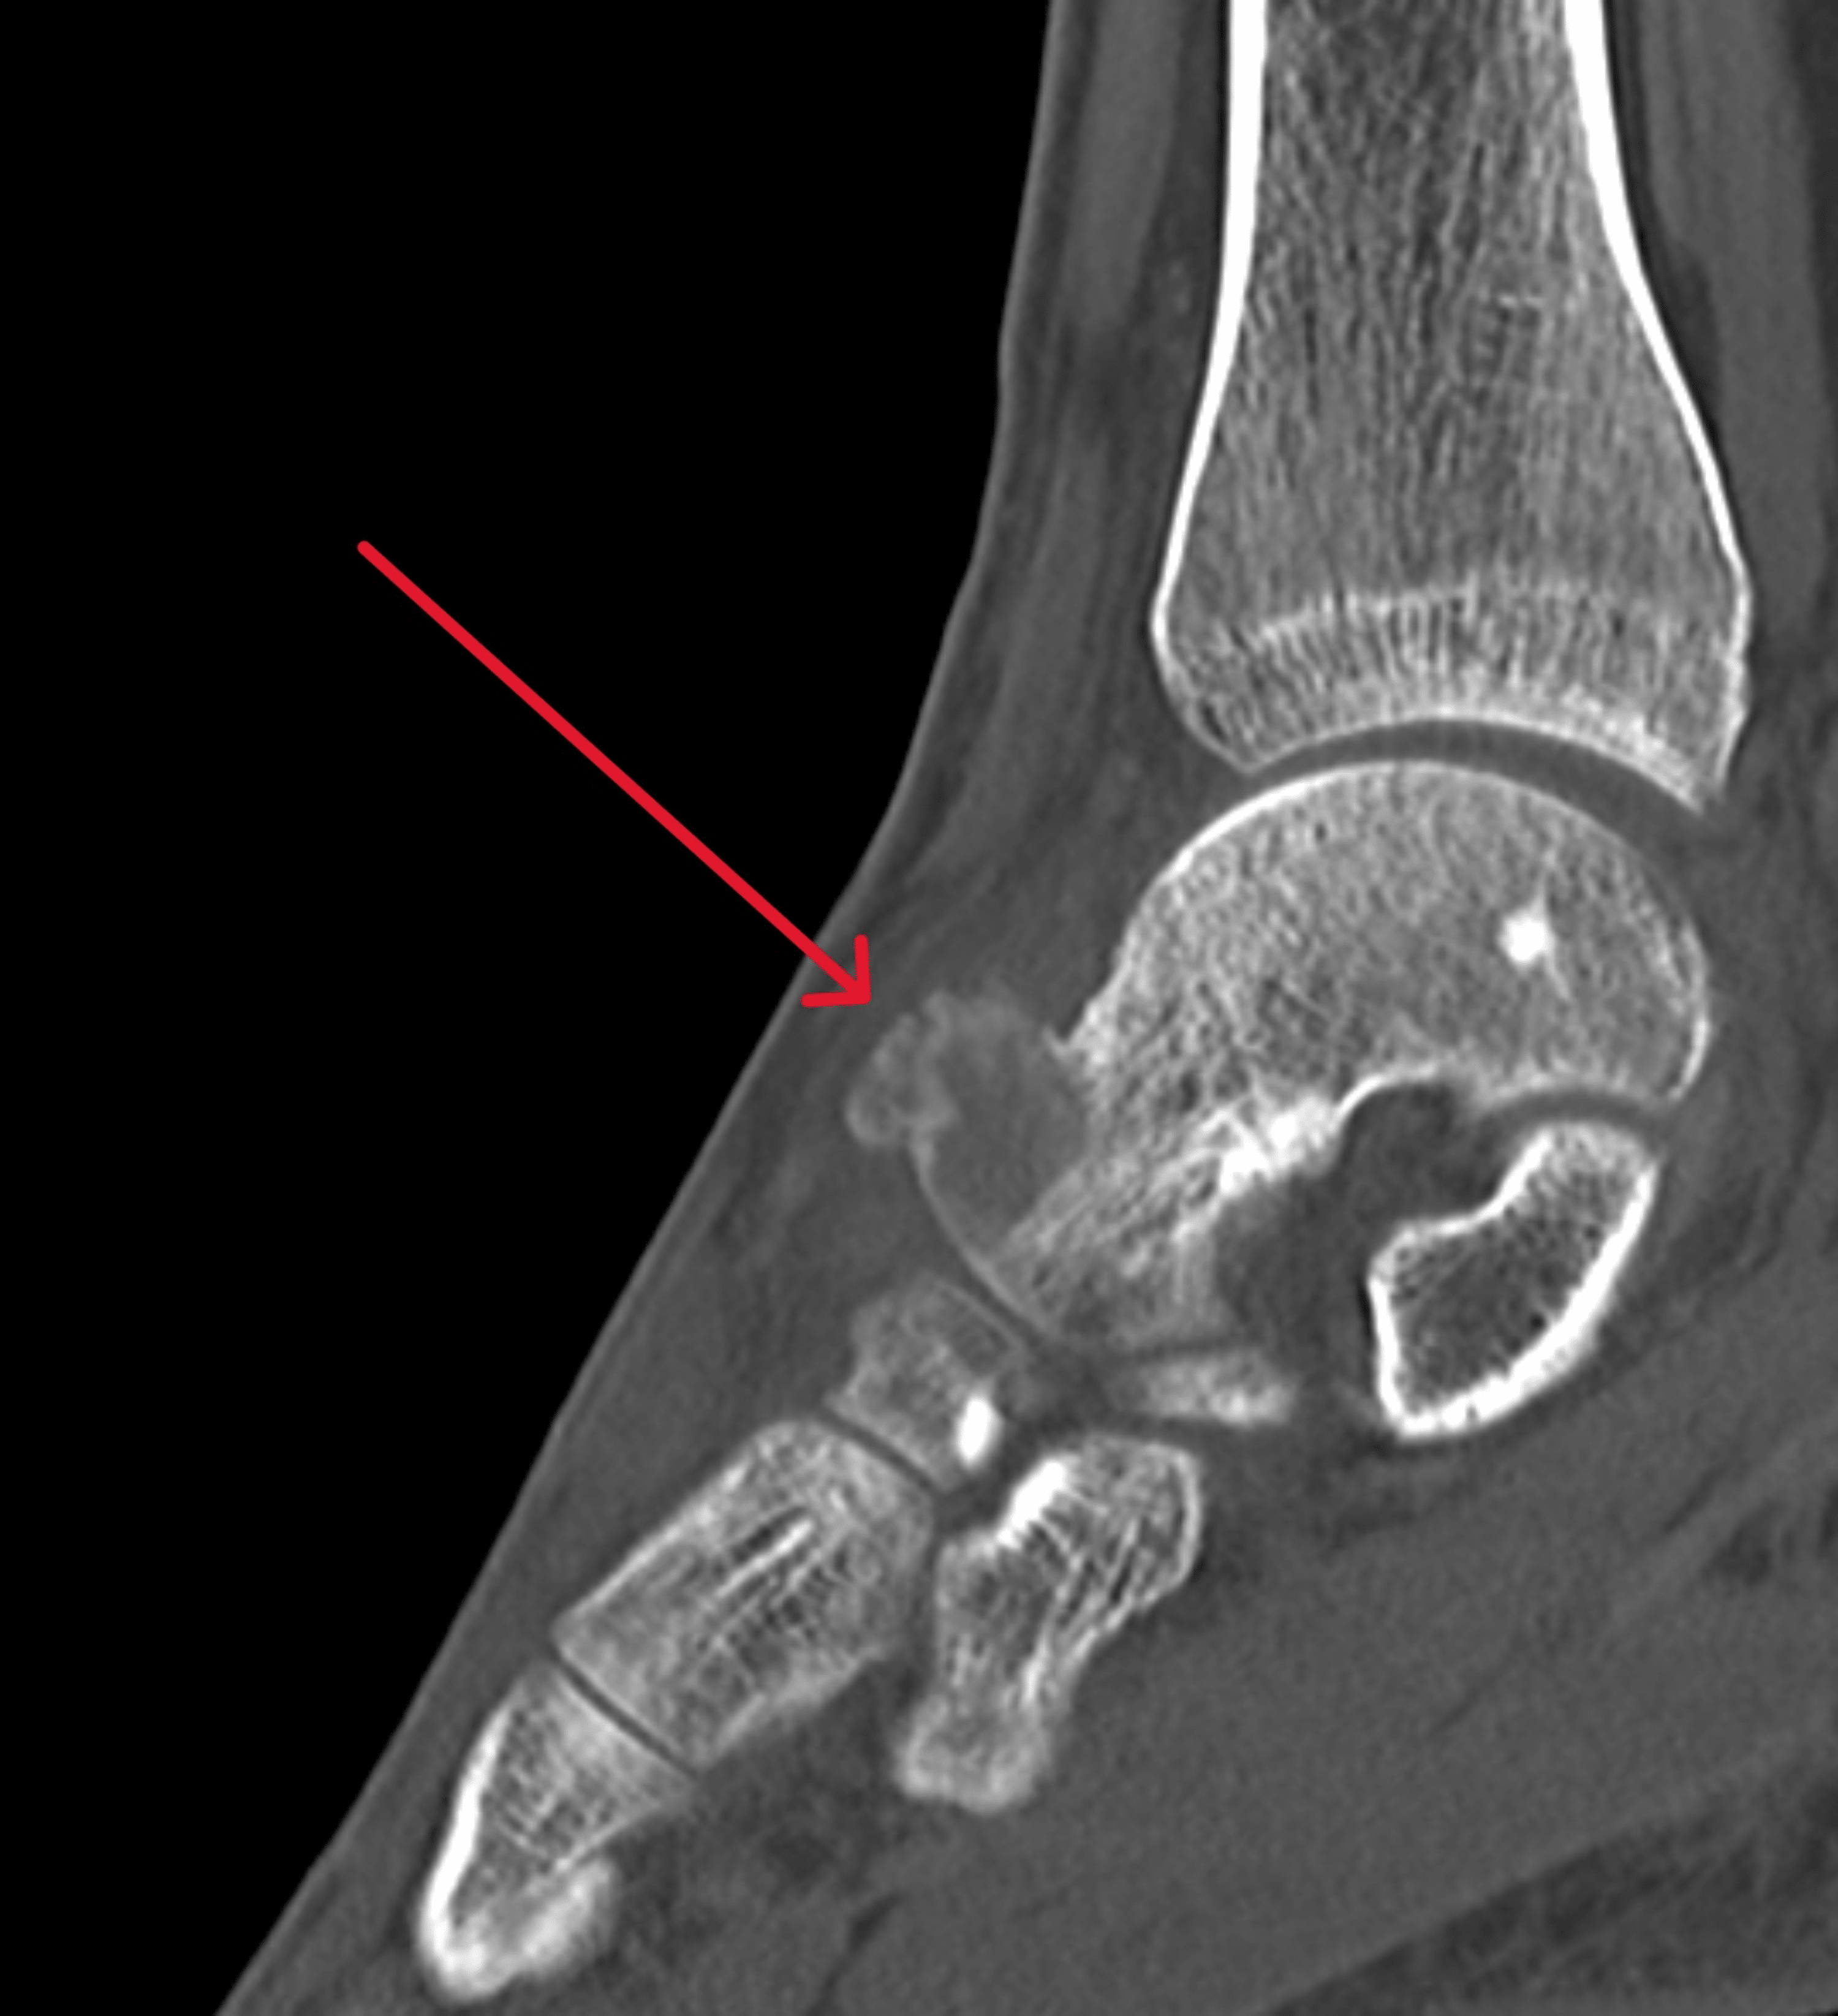

Talus Bone Cystic Lesion . (iia) cystic lesion with communication to talar dome surface; Point loading and loose bodies cause a synovitis, and the mechanics of the joint. (i) cystic lesion in talar dome with intact roof; Large bone cyst of the talar body frequently is associated with an osteochondral lesion (ocl). 1 it can be developed by the valve mechanism of the damaged. Osteochondral lesions of the talus (olt) remain a challenging pathology for the foot and ankle surgery community from diagnosis to. Each stage is defined as follows: Large uncontained lesions are usually painful as the structure of the talus is threatened.

Osteochondral lesion of talus with gout tophi deposition A case report Talus Bone Cystic Lesion Large bone cyst of the talar body frequently is associated with an osteochondral lesion (ocl). (iia) cystic lesion with communication to talar dome surface; 1 it can be developed by the valve mechanism of the damaged. Large uncontained lesions are usually painful as the structure of the talus is threatened. Osteochondral lesions of the talus (olt) remain a challenging pathology. Talus Bone Cystic Lesion.

Large cystic talar lesion case, receiving the surgery of osteochondral Talus Bone Cystic Lesion Osteochondral lesions of the talus (olt) remain a challenging pathology for the foot and ankle surgery community from diagnosis to. Each stage is defined as follows: Large bone cyst of the talar body frequently is associated with an osteochondral lesion (ocl). (i) cystic lesion in talar dome with intact roof; (iia) cystic lesion with communication to talar dome surface; Point. Talus Bone Cystic Lesion.

Management of bone cyst (BC) of talar body of the right ankle by Talus Bone Cystic Lesion (iia) cystic lesion with communication to talar dome surface; Each stage is defined as follows: Osteochondral lesions of the talus (olt) remain a challenging pathology for the foot and ankle surgery community from diagnosis to. Large bone cyst of the talar body frequently is associated with an osteochondral lesion (ocl). 1 it can be developed by the valve mechanism of. Talus Bone Cystic Lesion.